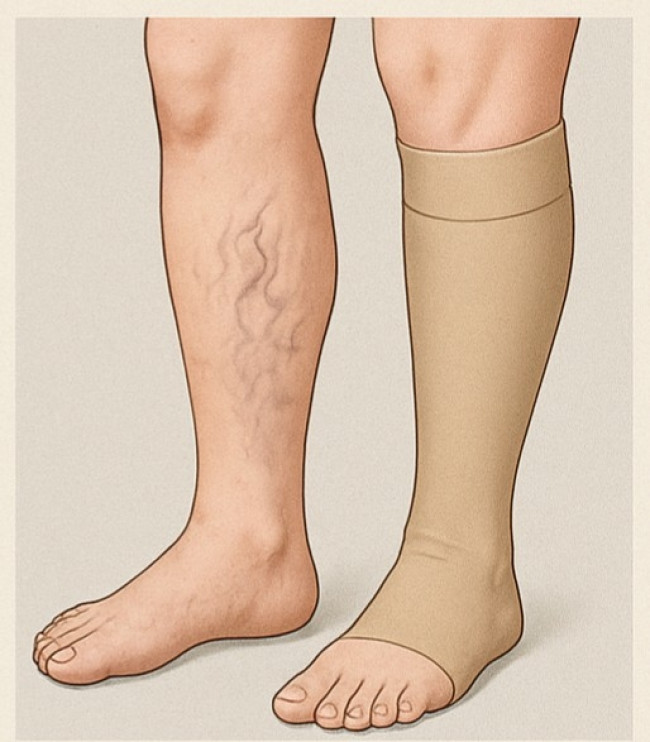

압박스타킹 착용하면 증상 개선 도움…"서 있을 땐 2∼3분마다 다리 움직여줘야"

이 중에서도 하지정맥류는 정맥부전을 대표하는 질환이다. 다리에 푸른 핏줄이 보이거나 혈관이 포도송이처럼 꼬이고 부풀어 오르는 증상이 특징이다.

보통 피부를 통해 보이는 정맥의 지름이 3㎜ 이상일 때를 하지정맥류로 진단한다.

치료는 보통 장시간 서 있거나 앉아 있는 자세를 피하면서, 정맥부전이 생긴 부위에 압박 스타킹을 착용하는 것부터 시작한다. 근육을 압박해 혈관을 수축하는 힘이 세지게 함으로써 혈액이 심장으로 다시 올라가도록 돕는 것이다.

스타킹은 길이를 무릎 아래 정도로 하고, 잠잘 때를 제외한 일상생활 동안 지속해 착용하는 게 바람직하다. 쉴 때 다리를 올린 채로 발끝을 얼굴 방향으로 당겼다 폈다 하는 운동을 반복하는 것도 증상 완화에 도움이 된다.